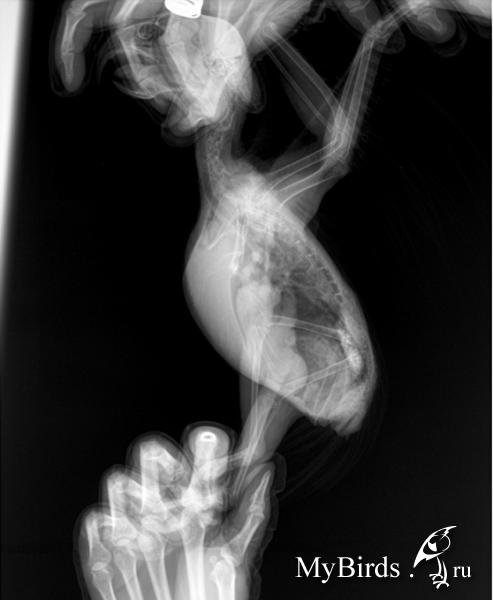

Zosia Опубликовано 2 апреля, 2017 #2 Опубликовано 2 апреля, 2017 Прямую проекцию переделать,то что вы ыложили-никуда негодное. По латеральной- яркие гранулемы как минимум, та кже мне не нравится смещение желудков низ (возможно гепатомегалия).Копрологию сделать- показатели мыла/жиры/жирные кислоты/крахмалы/лей\коциты*эритроциты/йодофильная флора/грибы. Бак.посев так же делайте, в Шанс-Био например. Надо исключить микоплазмоз- поэтому мазок из глотки на посев. Вероятность аспера очень велика...

Стерлиция Опубликовано 16 августа, 2017 #43 Опубликовано 16 августа, 2017 ВикторМ, гранулемы видны на рентгеновском снимке.

Leyaa Опубликовано 16 августа, 2017 Автор #44 Опубликовано 16 августа, 2017 ВикторМ, спасибо большое!У нас на снимке действительно видна пара гранулём.Но снимки не особо хорошего качества.А чтобы уточнить диагноз нужны 13000?.(((Я,к сожалению,в настоящее время не могу единовременно потратить такую сумму.(Тем более,что ЭКВИ,опытный врач,посоветовала нам особо не надеяться на благополучный исход при любом раскладе. Но,как знать,может чудо все таки произойдёт?!))) К результату мы пока не пришли т.к. ничем по сути не лечились.))Но устойчивый прогресс на лицо и это радует!) Стерлиция, гранулёмы видны.Но,к сожалению,не видно "активные" они или закальценированы.И по одному рентгену ставить диагноз-это,на мой взгляд,не совсем правильно.Но обследования стоят тоже нереально дорого.(Замкнутый круг...